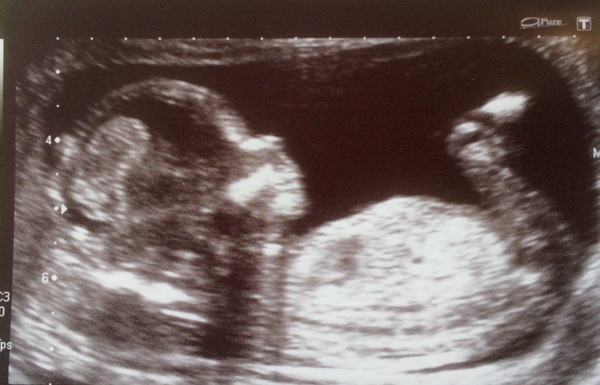

Lots of lovely scan Pics so thought I would share mine (which was yesterday). Small Nuchal fold measurement 1.4 and they said the baby looked good (huge relief). Still worried about the blood test but it was wonderful to see him or her for the first time! Wish I could just drop in for a look when I feel like it!

Just to let you know all good with our scan today Smile baby kicking away, so clear I was amazed how much we could see! Put me at 12&2, due date is 20th Dec. Please can I be added to the list when you're back from your jolly hols! Biscuit

Had my scan today and finally allowed myself to believe it's real. Had a MC at 9 weeks in Jan and have been panicking ever since we found out this time round!

Had scans at 7 and 9 weeks this time and although I saw a heartbeat, I was convinced I'd have a MMC this morning. But baby was there, bouncing around with a lovely heartbeat. I've exhausted myself today with the excitement now!

My dates put me at 12+1, but my scans put me at 13 which I'm quite relieved at. Due date is 15 December and I'm in north Bristol.

Had 12 week scan yesterday. All looks good. Am repeating the Harmony test- turns out you need 5% fetal DNA and I only had a low reading of 2.7% so they couldn't assess anything. Told my boss at work today- I transferred offices from another country in March so although very polite, I don't think he was best pleased! I have to formally let work know before 16 weeks which seems early, doesn't it?

Well had my scan today and all is as it should be. So happy, I can now start to enjoy my pregnancy. My due date has now move to 19th Dec.